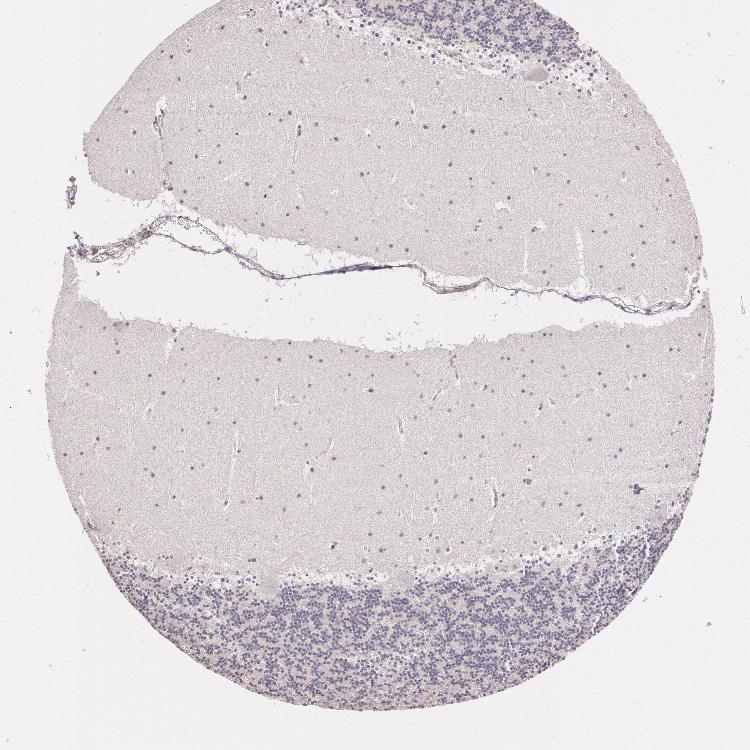

CEREBELLUM - Antibody stainingi

Antibody staining in the annotated cell types in the current human tissue is reported as not detected, low, medium, or high, based on conventional immunohistochemistry profiling in selected tissues. This score is based on the combination of the staining intensity and fraction of stained cells.

Each image is clickable and will lead to virtual microscopy that enables deeper exploration of all samples and also displays staining intensity scores, fraction scores and subcellular localization as well as patient and tissue information for each sample.

Antibody HPA001601

Purkinje cells Not detected

Cells in granular layer Not detected

Cells in molecular layer Not detected